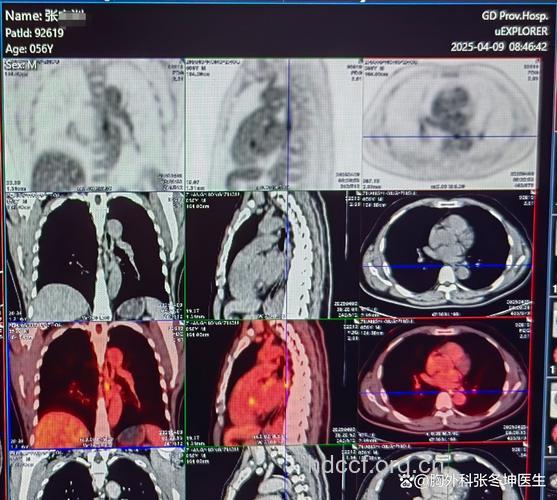

一旦发生上述不适症状,尤其是50岁以上者,应立即去医院就诊。食管癌的诊断手段很多,如食管黏膜脱落细胞检查,简单易行,常能发现一些早期病人,已成为早期发现食管癌的重要措施。另外,食管X线检查、内镜检查以及食管CT检查,不但能确定诊断,还能明确病灶的位置、肿瘤大小以及病灶的形态,有助于确定手术方式、放疗靶区及放疗计划。